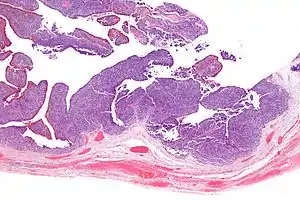

TCC of the ovary is diagnosed by examination of the tissue by a pathologist. It has a characteristic appearance under the microscope and distinctive pattern of immunostaining.[2]

It is not related urothelial carcinoma.[1] It is in the transitional cell category of ovarian tumours which also includes malignant Brenner tumour and benign Brenner tumour.

Very high mag.